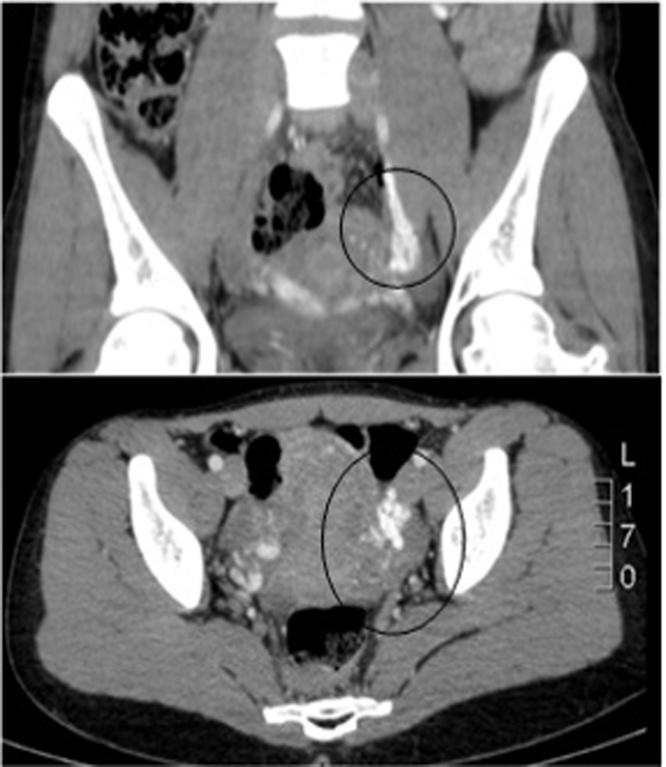

A 25 years old female patient with severe abdominal pain in the lower abdomen without hematuria. Diagnosis with nutcracker syndrome after performing computed tomography. Presented the first episode of pain with 17 years old and was diagnosed at age 25.

一名25岁女性患者,下腹部剧痛,但无血尿。经计算机断层扫描后诊断为胡桃夹综合征。患者17岁时首次出现疼痛症状,25岁时确诊。